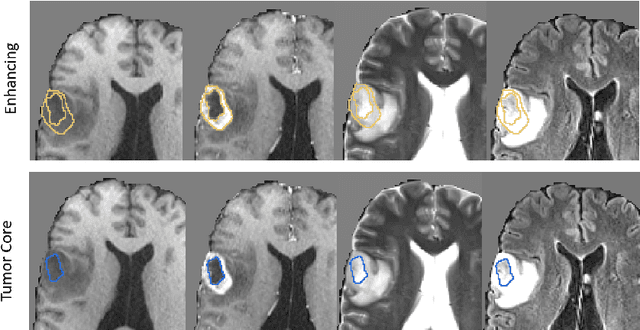

Abstract:Deep learning has quickly become the weapon of choice for brain lesion segmentation. However, few existing algorithms pre-configure any biological context of their chosen segmentation tissues, and instead rely on the neural network's optimizer to develop such associations de novo. We present a novel method for applying deep neural networks to the problem of glioma tissue segmentation that takes into account the structured nature of gliomas - edematous tissue surrounding mutually-exclusive regions of enhancing and non-enhancing tumor. We trained multiple deep neural networks with a 3D U-Net architecture in a tree structure to create segmentations for edema, non-enhancing tumor, and enhancing tumor regions. Specifically, training was configured such that the whole tumor region including edema was predicted first, and its output segmentation was fed as input into separate models to predict enhancing and non-enhancing tumor. Our method was trained and evaluated on the publicly available BraTS dataset, achieving Dice scores of 0.882, 0.732, and 0.730 for whole tumor, enhancing tumor and tumor core respectively.